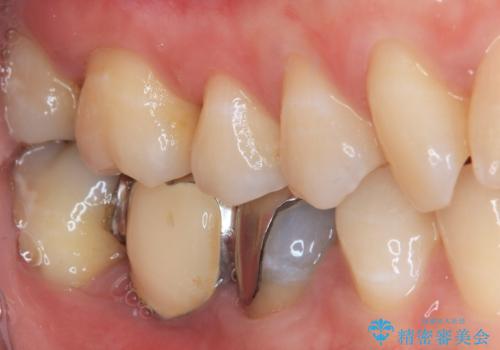

既に抜歯をして歯のない箇所にはインプラント治療をし、ブリッジの土台となっている歯のうち、手前側の小臼歯は既に根管治療をされている歯なのでオールセラミッククラウンへのやり替え、奥側の大臼歯はセラミックインレーへのやり替えをしていくこととしました。

患者様の希望、ブリッジの土台となっている歯の状態、インプラントとブリッジの比較などを総合的に判断して、今回のケースではインプラント治療を選択しました。